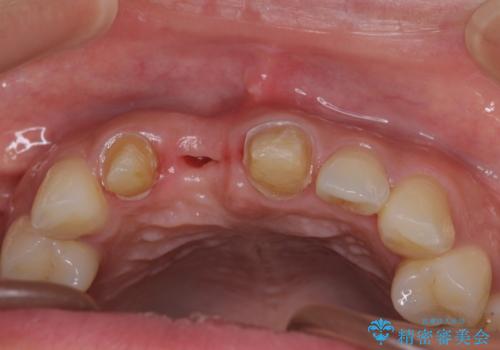

- 仮歯のまま前歯を放置しているとのことで来院された患者様です。

目視で確認できるほどしっかりとした破折が認められ、抜歯が必要と判断されました。

抜歯後は歯肉が痩せてしまうため、歯肉移植を行って歯肉の形態を改善した後、オールセラミックブリッジにて補綴することとしました。